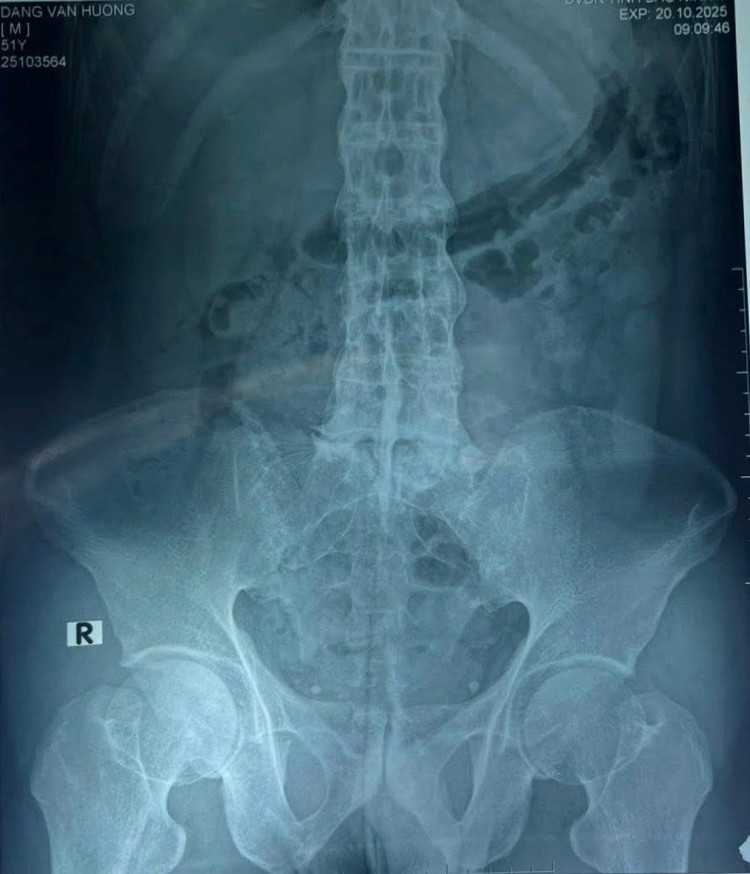

Hình ảnh cột sống của bệnh nhân trên phim chụp - Ảnh BVCC

Bệnh nhân nhập viện với chẩn đoán sỏi niệu quản trái 1/3 giữa và 1/3 trên, theo dõi nhiễm khuẩn niệu, viêm cột sống dính khớp, nang thận phải, sỏi thận trái. Cột sống bị dính cứng khiến khe gian đốt hẹp, việc chọc kim tủy sống trở nên vô cùng phức tạp.